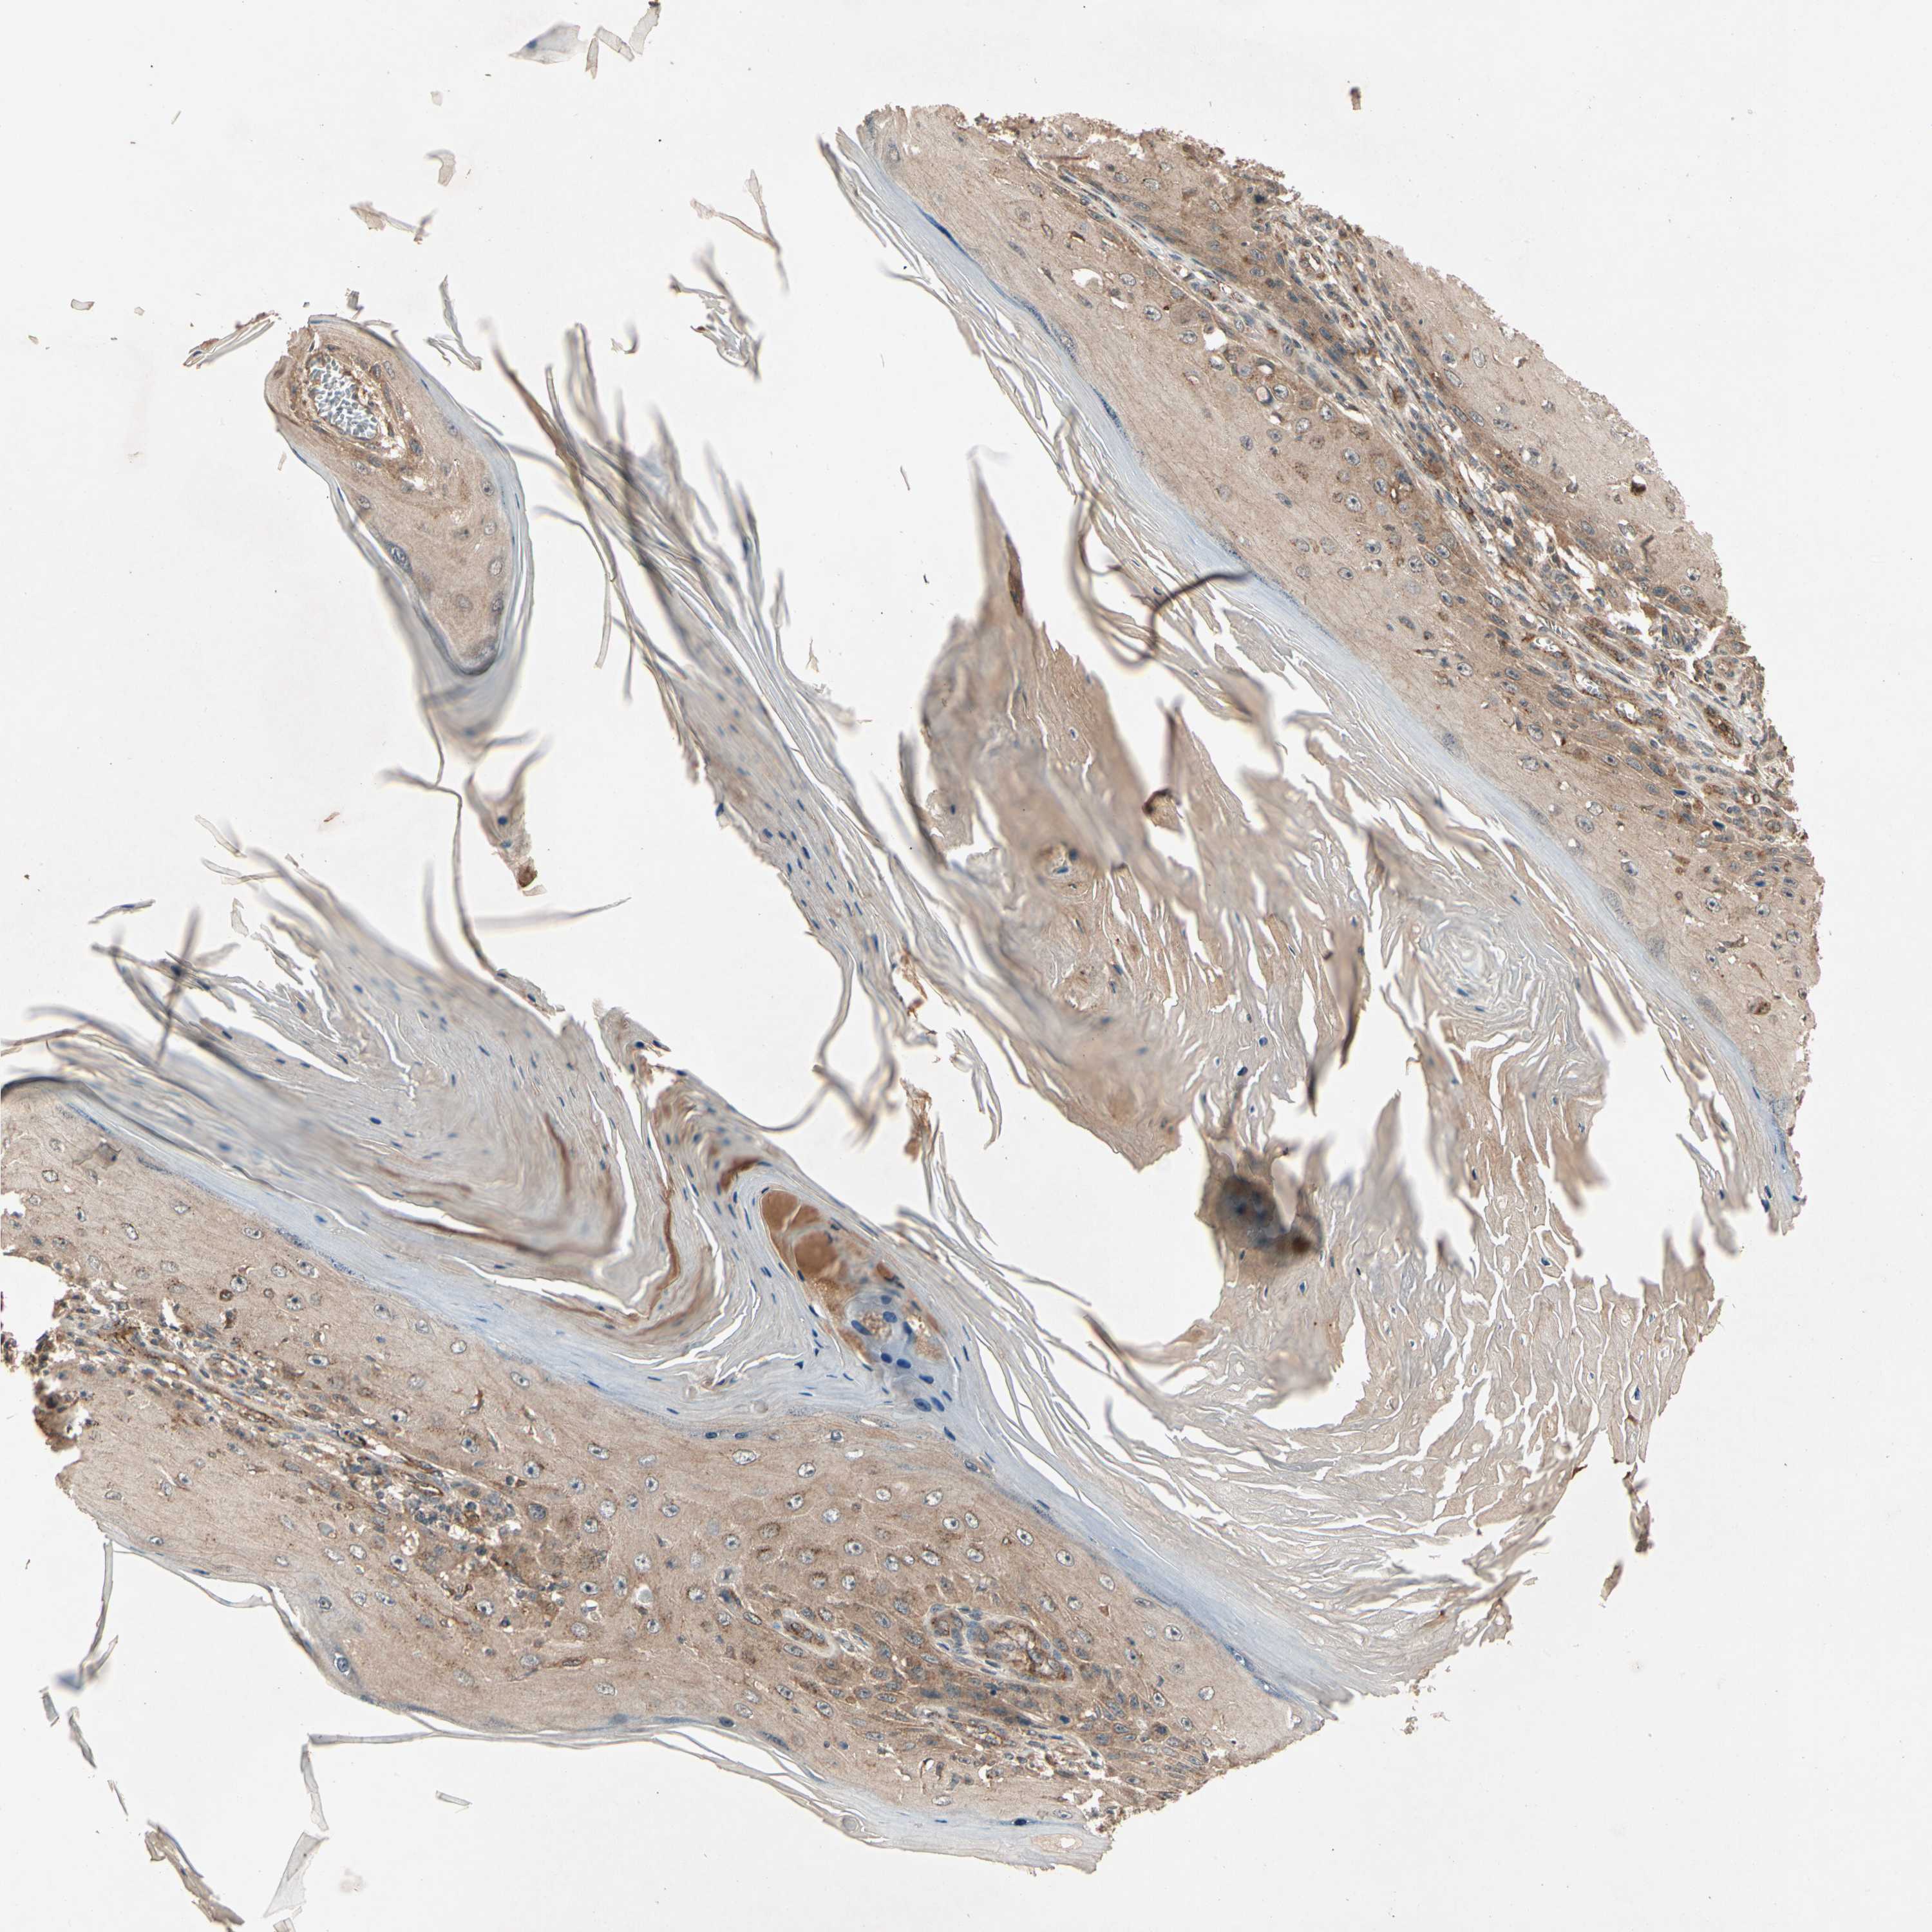

SKIN CANCER - Protein expressioni

A mouse-over function shows sample information and annotation data. Click on an image to view it in a full screen mode. Samples can be filtered based on level of antibody staining by selecting one or several of the following categories: high, medium, low and not detected. The assay and annotation is described here.

Antibody stainingi

Antibody staining in the annotated cell types in the current human tissue is reported as not detected, low, medium, or high, based on conventional immunohistochemistry profiling in selected tissues. This score is based on the combination of the staining intensity and fraction of stained cells.

Each image is clickable and will lead to virtual microscopy that enables deeper exploration of all samples and also displays staining intensity scores, fraction scores and subcellular localization as well as patient and tissue information for each sample.

Antibody CAB007766

Squamous cell carcinoma, metastatic, NOS